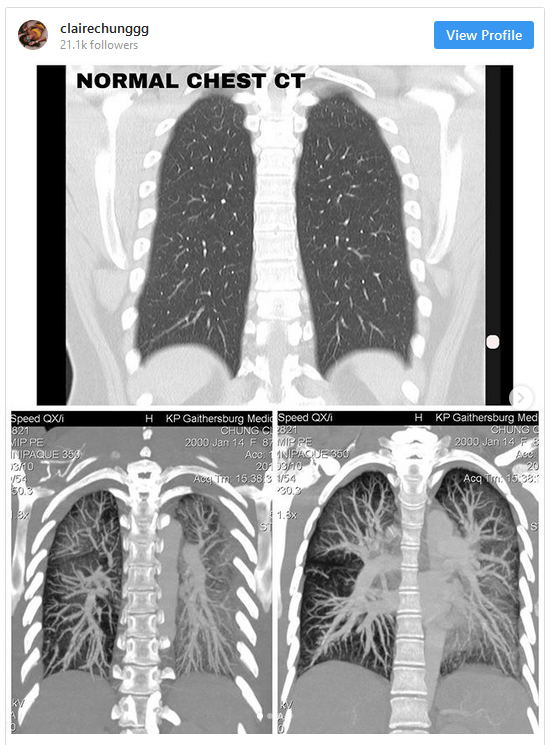

Berikutan itu, Claire sekali lagi memuat naik gambar yang menunjukkan imbasan sinar x pada paru-parunya yang kelihatan berkabus. Menerusi gambar imbasan paru-paru berkenaan, dapat dilihat bahawa kedua-dua belah paru-parunya kelihatan seperti berkabus, yang mana sepatutnya organ paru-paru yang sihat akan kelihatan jelas dalam imbasan.